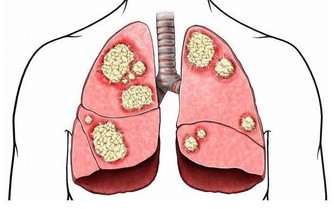

8、長期反復過度出汗明明沒有進行劇烈運動,卻在脖子、後背、頭皮、手心、腳掌大量出汗的話,可能是心髒病發作信號。

這種情況通常會持續超過一周的時間,或者在很長一段時間內反反复复的出現,

這種出汗類似感冒發熱,卻沒有其他感冒症狀。